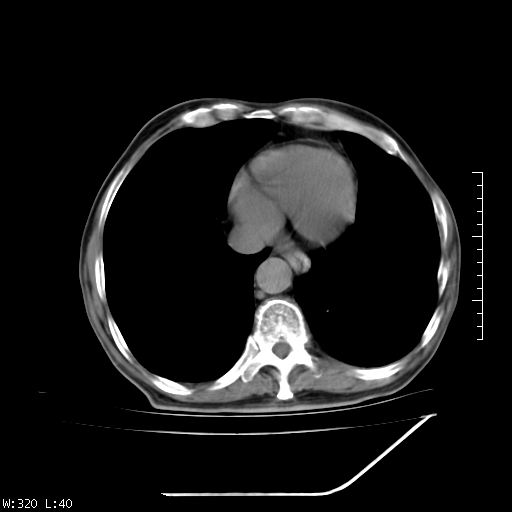

标题: CT23994:男、72、咳嗽、气短两月余,近来消瘦。 [打印本页]

标题: CT23994:男、72、咳嗽、气短两月余,近来消瘦。

右上肺实变,与胸膜关系密切,右肺容积缩小,隆突下淋巴结增大,考虑1 肺结核 2 肺癌

tb可能性大(双肺均可见片状密度增高灶,其内可见低密度空洞)。

右上肺大片状密度增高影,与胸膜关系密切,内见低密度透亮影,胸膜下可见三角形不张影,左下肺沿支气管走形结节影,纵膈内淋巴结显示。考虑结核并疤痕性不张可能性大,建议穿刺活检,排除肺泡癌。